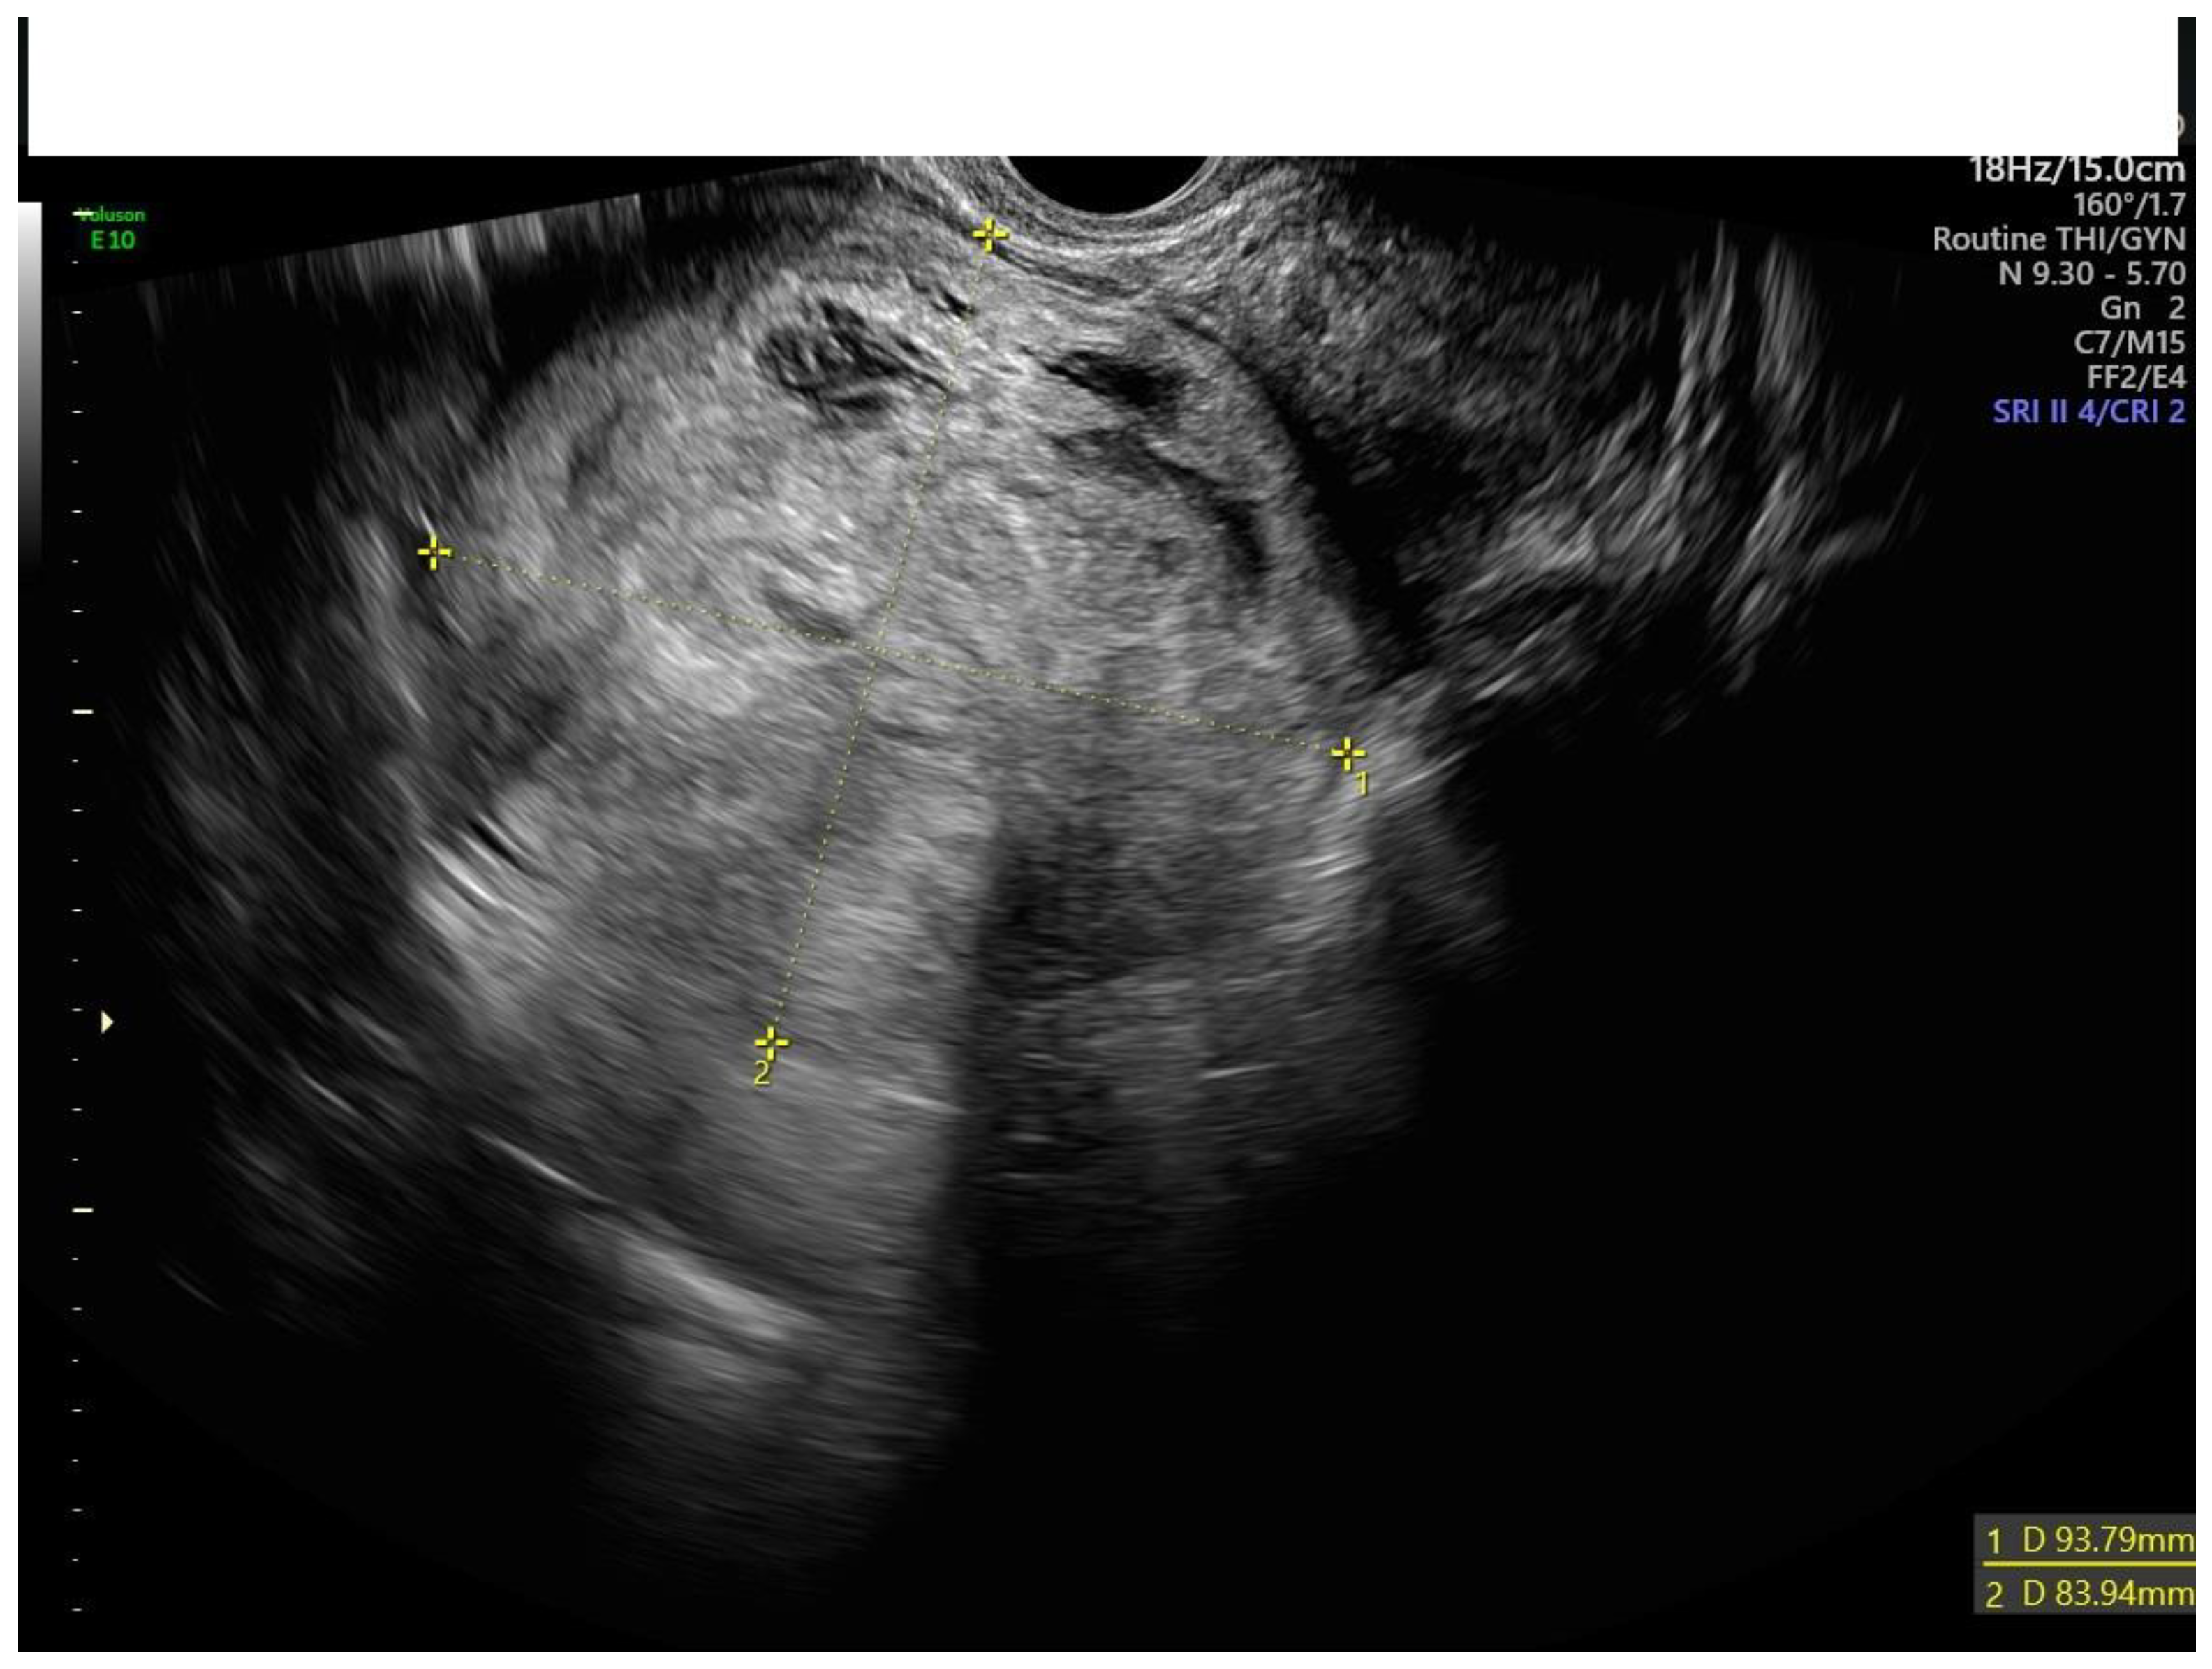

Figure 2.

Transvaginal ultrasound of a myoma with irregular cystic areas.